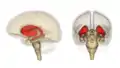

Анімоване зображення смугастого тіла

Смугасте тіло. Пряма й бокова проекції